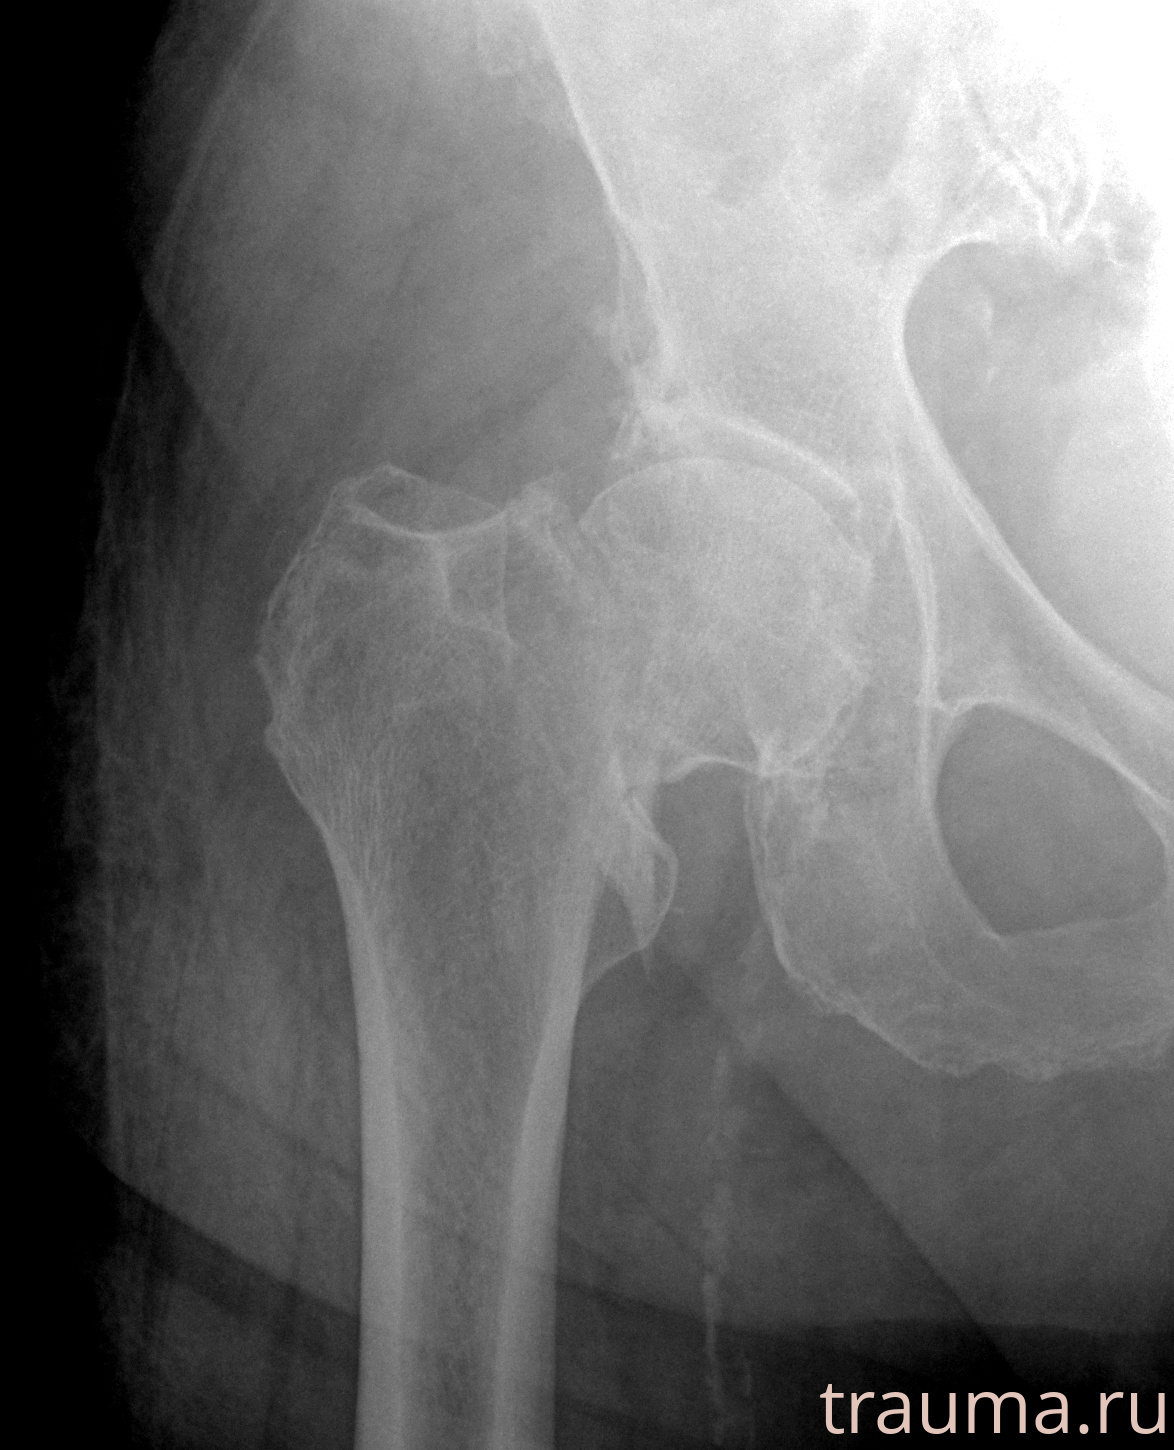

Первая помощь при переломе шейки бедра

Рентгенограммы